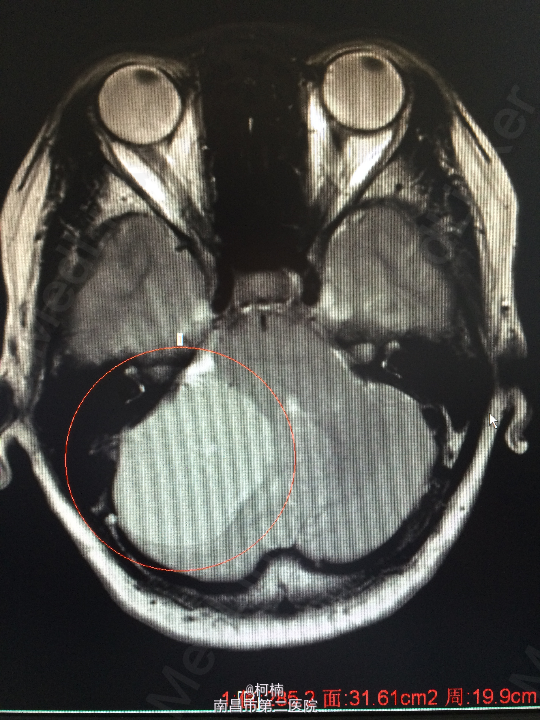

主诉:反复头晕、头痛伴呕吐及行走不稳10月余 病史:患者老年女性,55岁,10余月前开始出现头晕、头痛伴呕吐及行走不稳,无肢体乏力、肢体抽搐、意识障碍等不适,于当地医院诊治行头颅MR提示:右侧小脑角占位,考虑肿瘤。 查体:神经系统体查未见明显异常

查体:神经系统体查未见明显异常 辅助检查:头颅MR提示右侧桥小脑区占位性病变,考虑脑膜瘤。四脑室狭窄,变形,幕上脑室积水,小脑扁桃体疝

诊断:右侧小脑脑膜瘤 处理:先行介入栓塞肿瘤供血动脉,再行开颅手术治疗,术后予组织病理检查,提示:脑膜瘤